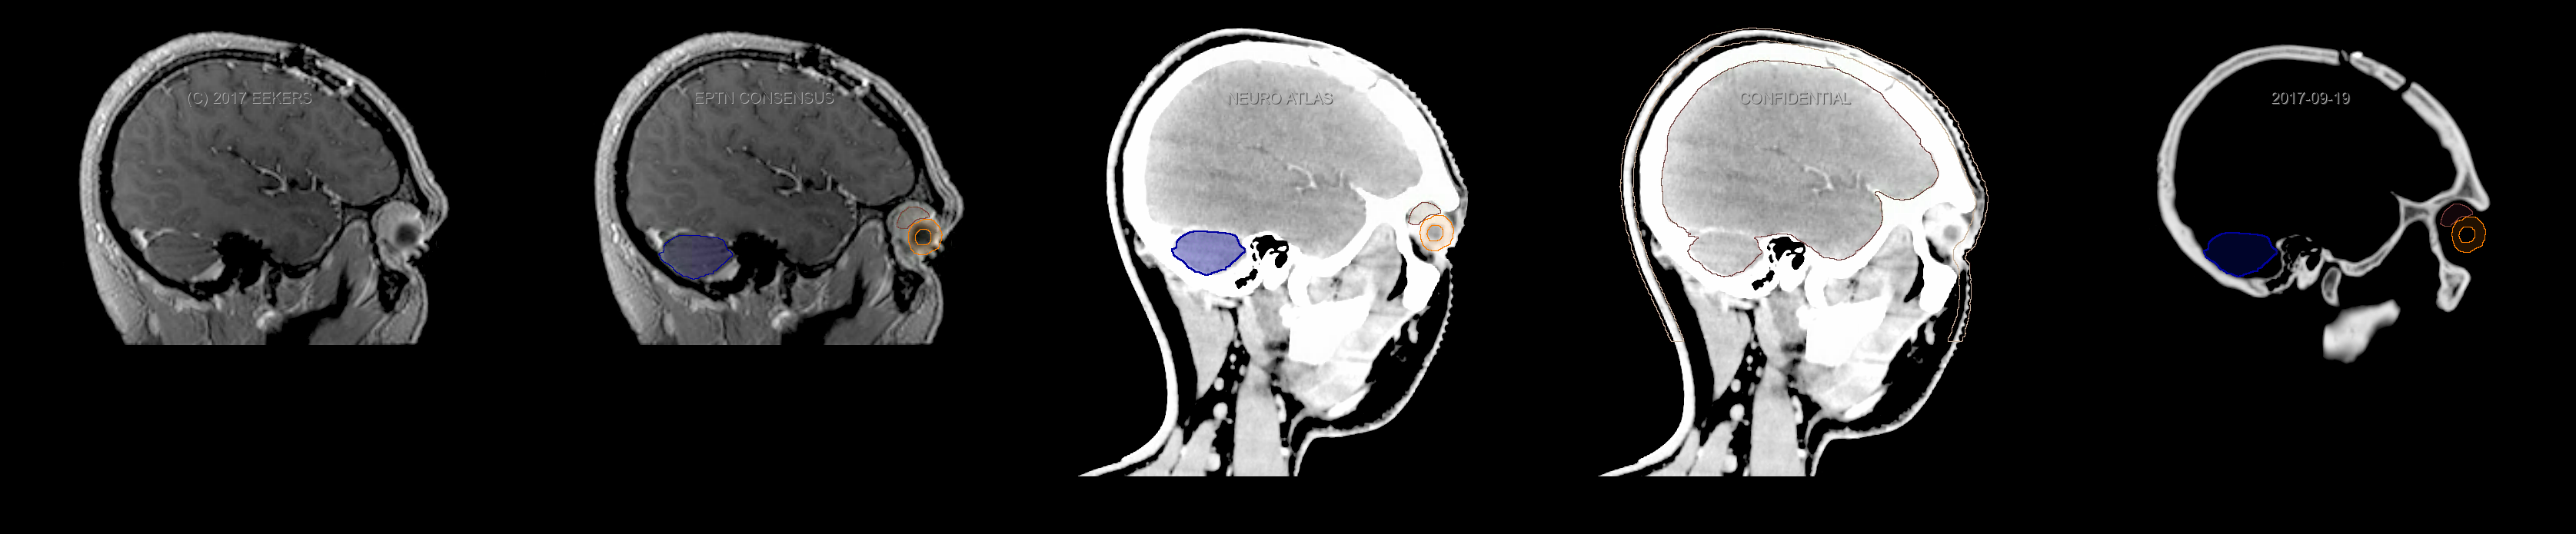

Three-dimensional delineation of the fifteen consensus OARs for neuro-oncology are shown on CT and 3 Tesla (3T) MR images (slice thickness 1 mm with intravenous contrast agent). All are presented in transversal, sagittal and coronal view.

From left to right: MR without structures, MR with structures, CT (WW/WL 120/40) with structures, CT (WW/WL 120/40) with Brain and Brainstem Surface, CT (WW/WL 1500/120)with structures